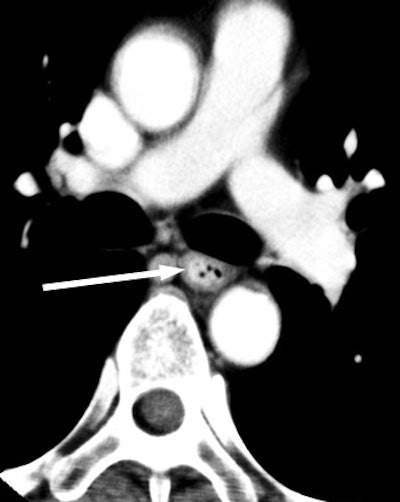

![]() |

| Venous-phase image of 64-year-old male with T3 esophageal cancer. On this phase, the tumor can be seen as well. |

"In the atrial contraction period, we could observe a low-density band between the left atrium and the (esophageal cancer), but it was undetectable in the end-systolic phase," he said. "The low-density band between the (left atrium) and the (esophageal cancer) in the 70% to 80% portions of the RR interval could be visualized in all 12 subjects; however, it was not visualized in the 40% portion in any of the subjects."

"The left atrium contracts separately from the esophageal cancer, and we concluded that the tumor does not invade the left atrium," Shuto said. "(The case was) diagnosed as T3. All 12 subjects underwent esophagectomy, and all revealed squamous cell carcinomas. No one had evidence of esophageal cancer invasion of the left atrium in histological findings."

Thus, the negative predictive value was 100% for identifying pericardial invasion. "We predicted if a low-density band between left atrium and the esophageal cancer is visualized, the tumor will be stage T3 cancer.... ECG-gated multislice CT can reduce the influence of cardiac pulsation," he concluded.